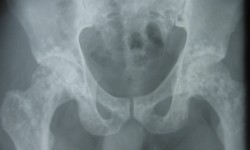

OSTEOPOIKILOSIS By Admin | December 20, 2013 - 6:32 am | Musculoskeletal, Skeletal Dysplasias Leave a comment FIG. 1 Chest P A Fig.2-Rt.Shoulder A.P FIG. 3-LtShoulder A. P Fig.4 Both hands A. P Fig. 5 Female Pelvis FIG.6 Pelvis A.P-Male FIG. 7-Both knee A. P FIG.8 Left ankle with leg A.P